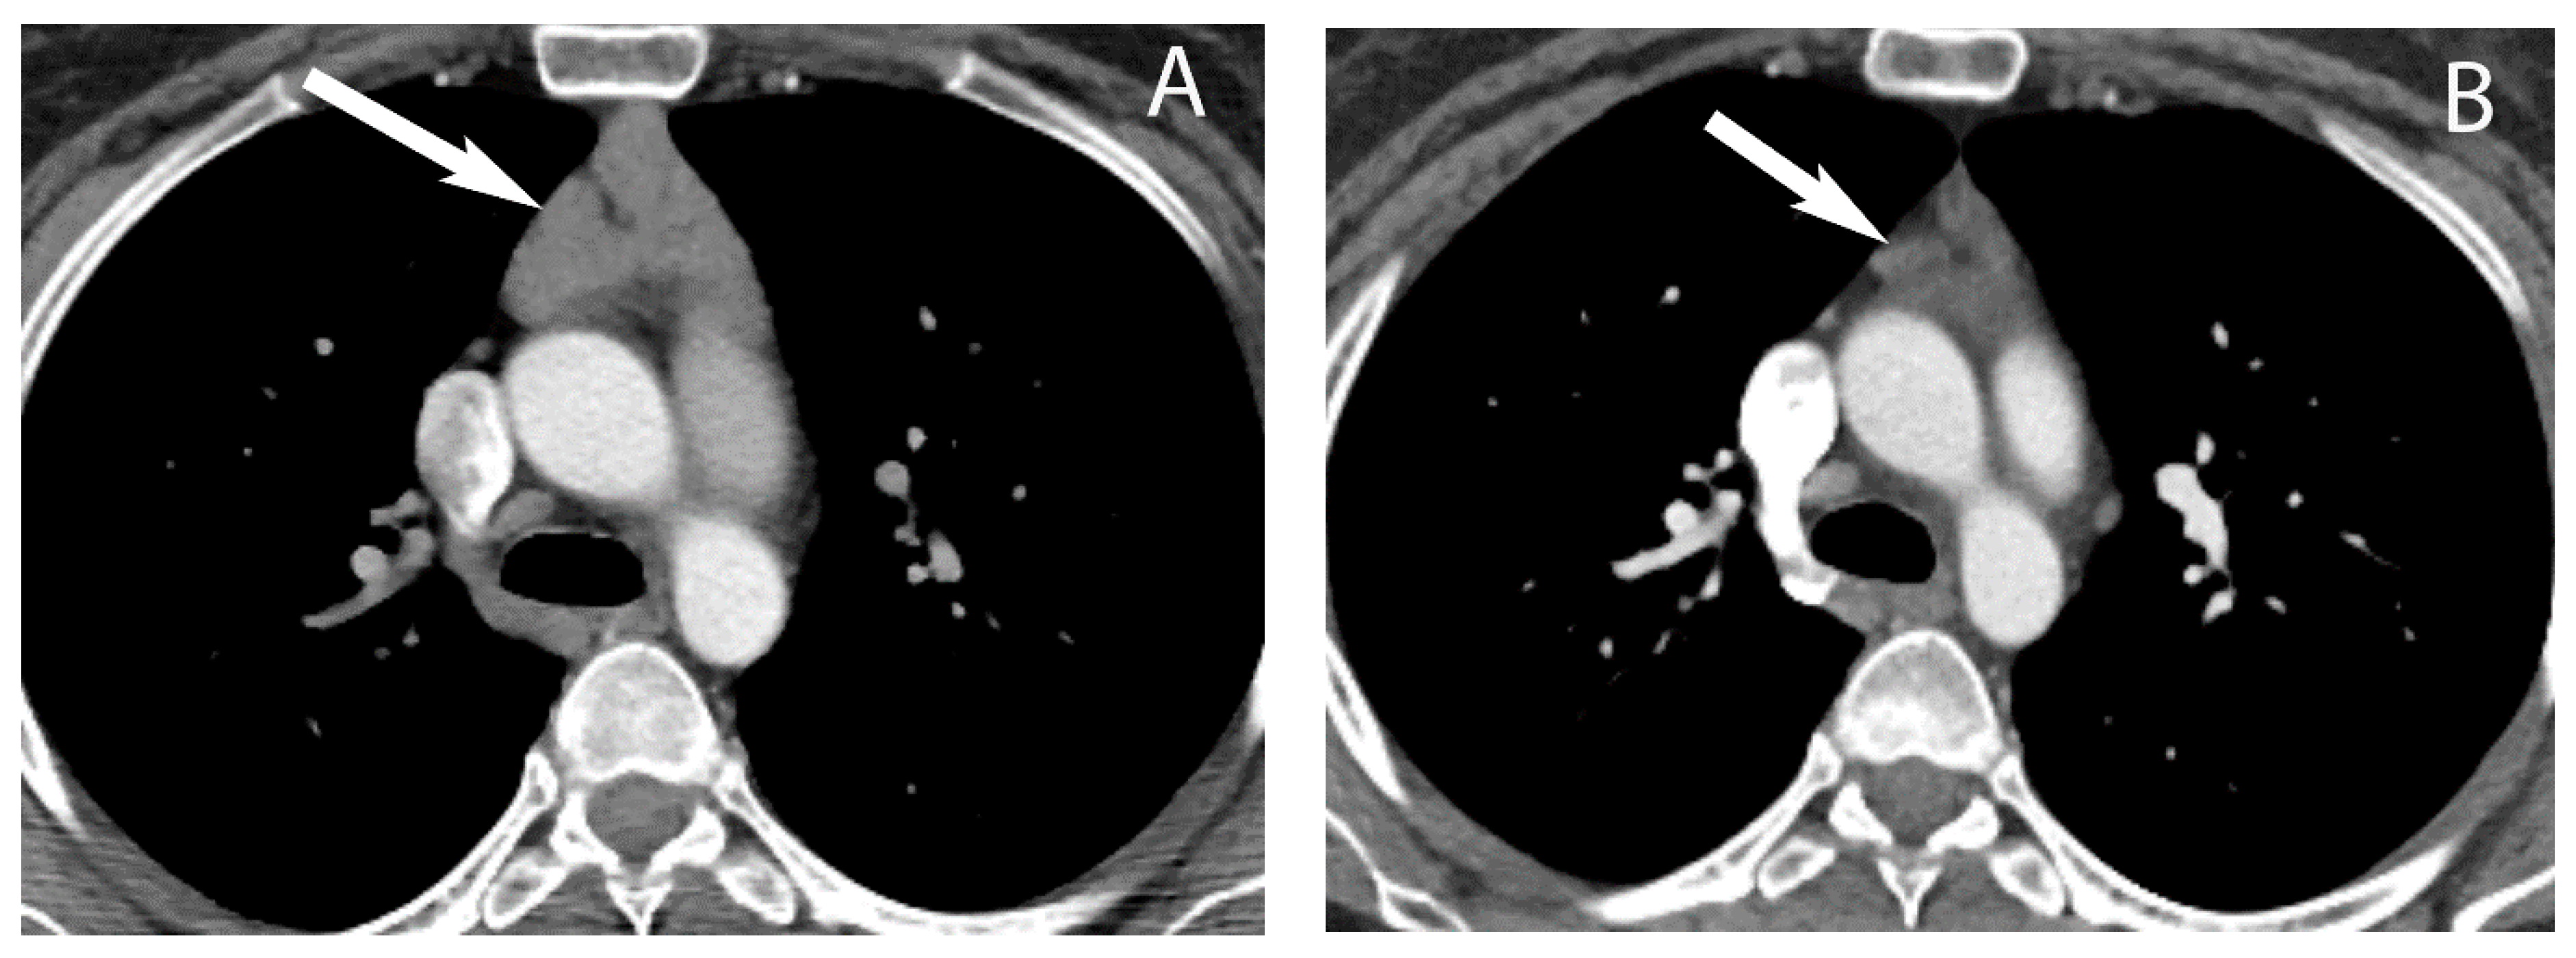

3. Cystic Lesions

6. Lymphoma

8. Cystic Lesions